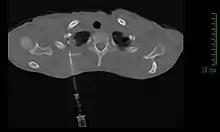

Tomodensitométrie

Le scanner thoracique permet d'analyser avec précision la localisation de la tumeur, de mesurer sa taille, et de rechercher des adénopathies médiastinales[11]. Idéalement, il doit être injecté d'un produit de contraste iodé afin de préciser les rapports vasculaires[11].

La méthode de diagnostic la plus précise est la ponction percutanée trans-thoracique par ponction à l’aiguille, sous contrôle scanner, qui présente un rendement de 95 %[11],[21]. En cas d'échec, il est possible de réaliser une biopsie chirurgicale par thoracoscopie ou thoracotomie[11].